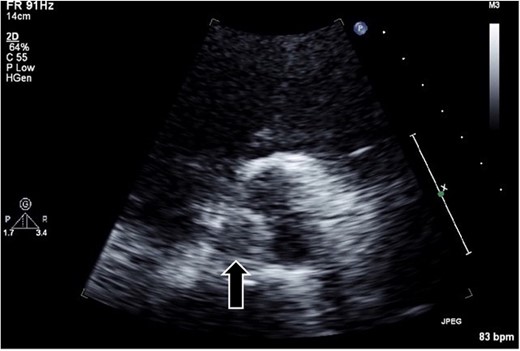

The surgical procedure employed a median sternotomy, with creation of cardiopulmonary bypass via cannulation of the ascending aorta and right atrium. After cross-clamping, cold antegrade cardioplegia was administered. Upon aortic valve exposure, a 2 × 2-cm vegetation was noted on the noncoronary cusp (Figs 2 and 3). The vegetation was quickly removed, and the noncoronary cusp was preserved. Following a 50-min bypass time, with a 35-min cross-clamp time, the patient was successfully weaned off bypass with minimal inotropic support. A portion of the vegetation was sent for culture; however, no bacterial or fungal growth was detected. Further histopathologic examination revealed a fibrin-rich thrombus containing red blood cells with organization at the periphery (Fig. 4).

A 2 × 2-cm vegetation is observed on the noncoronary cusp of the aortic valve.